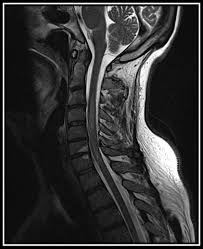

A fatty tissue called myelin protects these nerve fibers. Longitudinally extensive spinal cord lesions (lescl), also known as longitudinally extensive transverse myelitis (letm), represent extensive involvement of the spinal cord, with abnormal t2 signal traversing at least three vertebral body segments in length. Tm is characterized by weakness and numbness of the limbs. Transverse myelitis is not a single process but rather a syndrome with multiple causes. The spinal cord also carries sensory information back to the brain. It results from damage to nerve cells in a certain area. Transverse myelitis is an inflammation of your spinal cord. Transverse myelitis is typically characterized by subacute onset of motor weakness and sensory changes with or without bowel or bladder dysfunction. He has recovered and remains well. A spinal sensory level is usually detected on physical examination. Sagittal t2wi through the cervical spine demonstrates a longitudinally extensive segment of… Weakness, sensory disturbance, and autonomic dysfunction evolve over hours or days, most progressing to maximal clinical severity within 10 days of onset. Transverse myelitis (tm) is a rare neurological condition in which the spinal cord is inflamed.

He has recovered and remains well. 2 article feature images from this case 44 public playlist includes this case Transverse myelitis may occur in isolation or in the setting of another illness. Overall features are fairly typical of transverse myelitis, and the patient has been followed both clinically and with mri. Sagittal t2wi through the cervical spine demonstrates a longitudinally extensive segment of…

Idiopathic transverse myelitis is a Longitudinally extensive transverse myelitis (letm) is a specific subtype of acute transverse myelitis that usually affects three or more vertebral levels and produces marked neurological deficits. Partial transverse myelitis and partial myelitis are terms sometimes used to specify inflammation that only affects part of the width of the spinal cord. Weakness, sensory disturbance, and autonomic dysfunction evolve over hours or days, most progressing to maximal clinical severity within 10 days of onset. Imaging studies of the spine ruled out an infective focus and no other lesions were seen within the cord. No significant medical history other than a mild upper respiratory infection a few weeks prior. Figure 93a figure 93b figure 93c findings figure 93a: Clinical and first mri were both favoring the diagnosis of transverse myelitis, after which the patient received corticosteroid treatment. Transverse myelitis (tm) is a rare neurological condition in which the spinal cord is inflamed. Tm is characterized by weakness and numbness of the limbs. Although any cord level can be affected, the classic description includes a preference for the thoracic cord 14. When it occurs without apparent underlying cause, it is referred to as idiopathic. Sagittal t2wi through the cervical spine demonstrates a longitudinally extensive segment of…